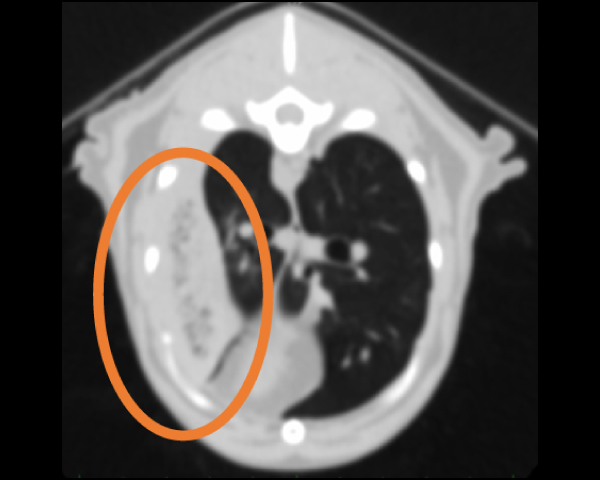

脾臓の多発性吸収結節像を確認

CT検査にて肺野のマイクロバブル所見